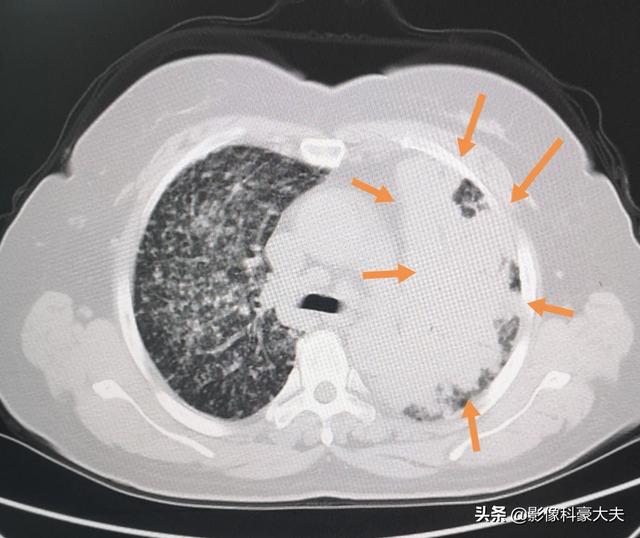

Il s'agit aujourd'hui d'une autre patiente qui a subi un repas baryté pour vérifier son estomac parce qu'elle n'aimait pas manger, ce qui a donné lieu à une fluoroscopie qui a révélé des ombres se développant dans ses poumons, suivie d'un scanner thoracique qui a confirmé le diagnostic de cancer du poumon avancé avec des métastases étendues. ......